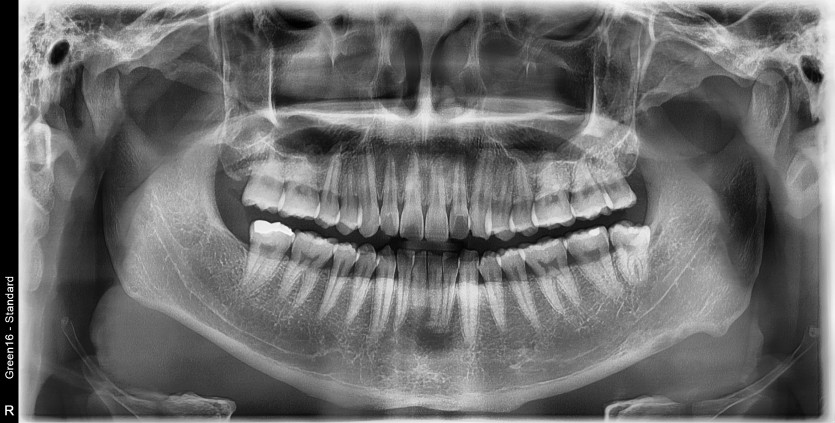

#28,38 사랑니 발치

구강 외과 전문의가 당일 발치했습니다.